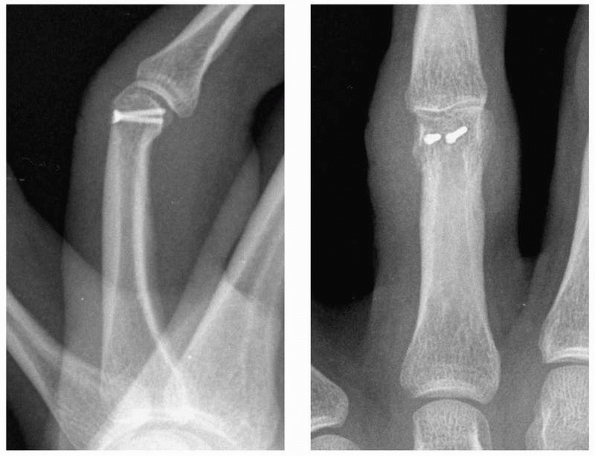

Stable fixation is achieved with either internal plate (Fig. 28-4)

FIGURE 28-4 When segmental bone loss occurs (A), shortening may be prevented by temporary stabilization (B). Subsequent internal fixation (C, D) and bone grafting can restore the original anatomic parameters of the skeletal unit.